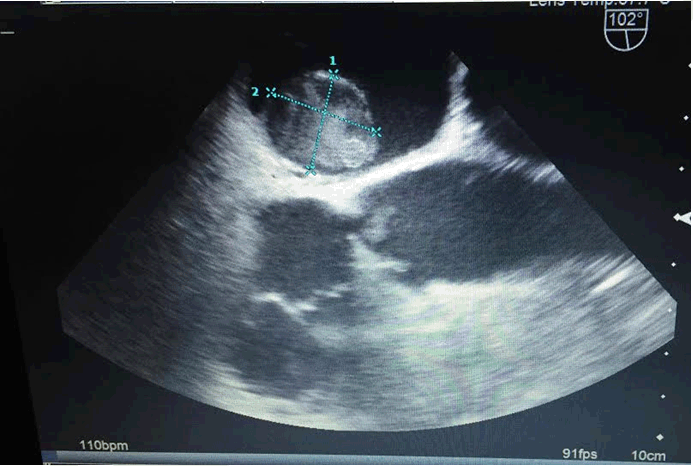

The initial treatment plan was surgical removal of the tumor upon recovery from her spinal surgery. However, the patient declined treatment and failed to follow-up for serial TEE's. Two years later, she returned complaining of episodic chest tightness precipitated by anxiety as well as increased dyspnea upon exertion. Repeat TEE revealed the atrial mass had enlarged to 2.2x2.0 cm in size (Figure 1).

Figure 1: Second TEE of our patient's left atrial mass. The TEE demonstrates a 2x2.2 cm mass in the left atrium. This TEE was done 30 months after the atrial myxoma was first noted.